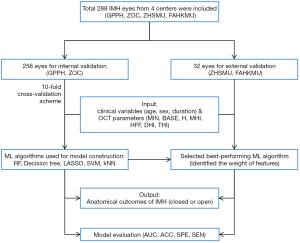

A total of 1,792 preoperative macular OCT parameters and 768 clinical variables of 256 eyes from both the Department of Ophthalmology, GPPH (378 preoperative OCT parameters and 162 clinical variables of 54 eyes), and Zhongshan Ophthalmic Center (ZOC, 1,414 preoperative OCT parameters and 606 clinical variables of 202 eyes) were used for ML training and internal validation. For external validation, 224 preoperative macular OCT parameters and 96 clinical variables of 32 eyes from the Department of Ophthalmology, Zhujiang Hospital of Southern Medical University (ZHSMU, 35 preoperative OCT parameters and 15 clinical variables of five eyes), and the Department of Ophthalmology, the First Affiliated Hospital of Kunming Medical University (FAHKMU, 189 preoperative OCT parameters and 81 clinical variables of 27 eyes), were included.

To develop a ML model for the accurate prediction of postoperative IMH status, five ML algorithms were trained: random forest (RF) (23), decision tree (24), support vector machine (SVM) (25), k-Nearest Neighbor (KNN) (26), and least absolute shrinkage and selection operator (LASSO) (27). For these algorithms, the inputs were OCT parameters (BASE, MIN, H, MHI, THI, THI, and HFF) and clinical variables (age, sex, and duration of symptoms), while the output was postoperative IMH status (i.e., closed or open).

In the internal validation, the area under the receiver operating characteristic (ROC) curve (AUC), accuracy, specificity, and sensitivity were generated after each run of the ten-fold CV. The mean values of the ten runs were recorded to measure the overall performance of our ML models. The predictive power of the best-performing ML algorithm was determined in the internal validation and was further verified by our independent external validation dataset. The flowchart is shown in Figure 2.